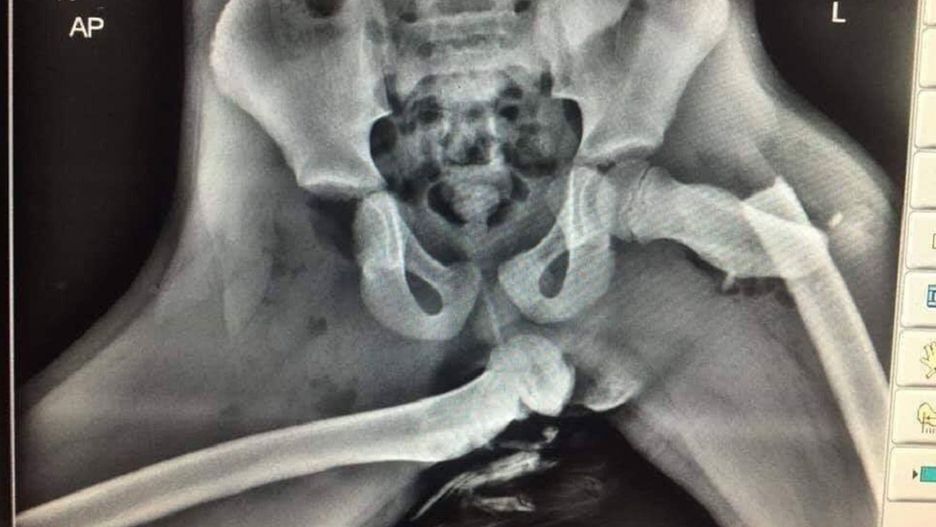

Policjant z Walii opublikował w sieci szokujące zdjęcie rentgenowskie. Widać na nim skalę obrażeń odniesionych przez młodą kobietę, która w czasie wypadku trzymała nogi na desce rozdzielczej.

Sierżant Ian Price z Dyfed-Powys Police w Walii postanowił ostrzec ludzi, by w czasie jazdy samochodem nie kładli nóg na desce rozdzielczej. Jako przestrogę opublikował zdjęcie rentgenowskie, na którym widać obrażenia ofiary wypadku samochodowego.

Oto zdjęcie rentgenowskie okropnych obrażeń odniesionych przez pasażerkę z przedniego siedzenia, która trzymała stopy na desce rozdzielczej. Jeśli zobaczysz, że twój pasażer to robi, zatrzymaj pojazd i pokaż mu to zdjęcie - napisał na Twitterze Ian Price.

Jedno z bioder młodej kobiety zostało złamane, a drugie zwichnięte. Pasażerka przeżyła, ale jej obrażenia zostały określone jako "zmieniające życie".